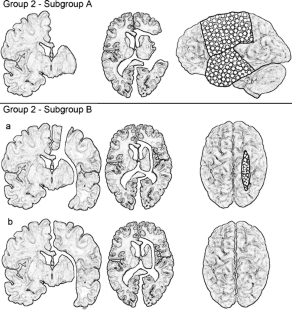

Fig. 2

Fig. 3 a–e